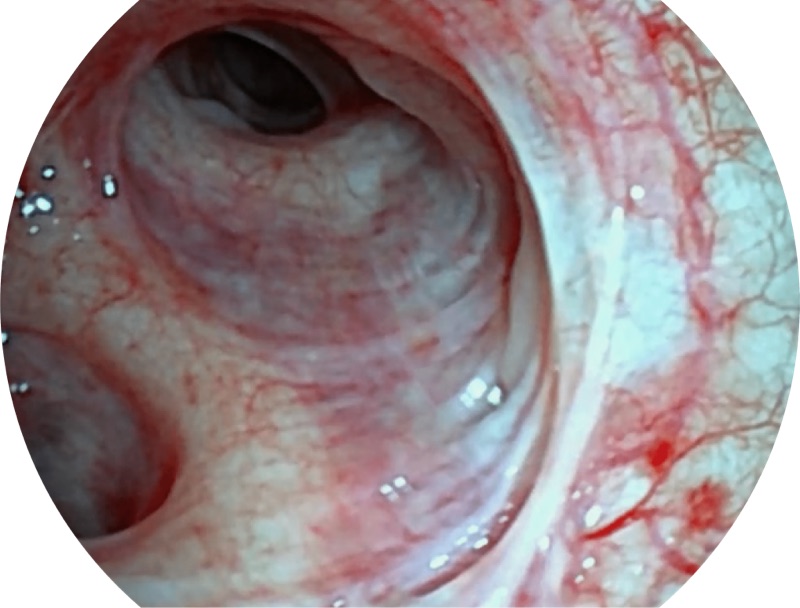

帮助医生更加清晰地观察气管表面病灶

EB-5H20具有4.9mm外径及2.0mm钳道提升对外围支气管检查能力